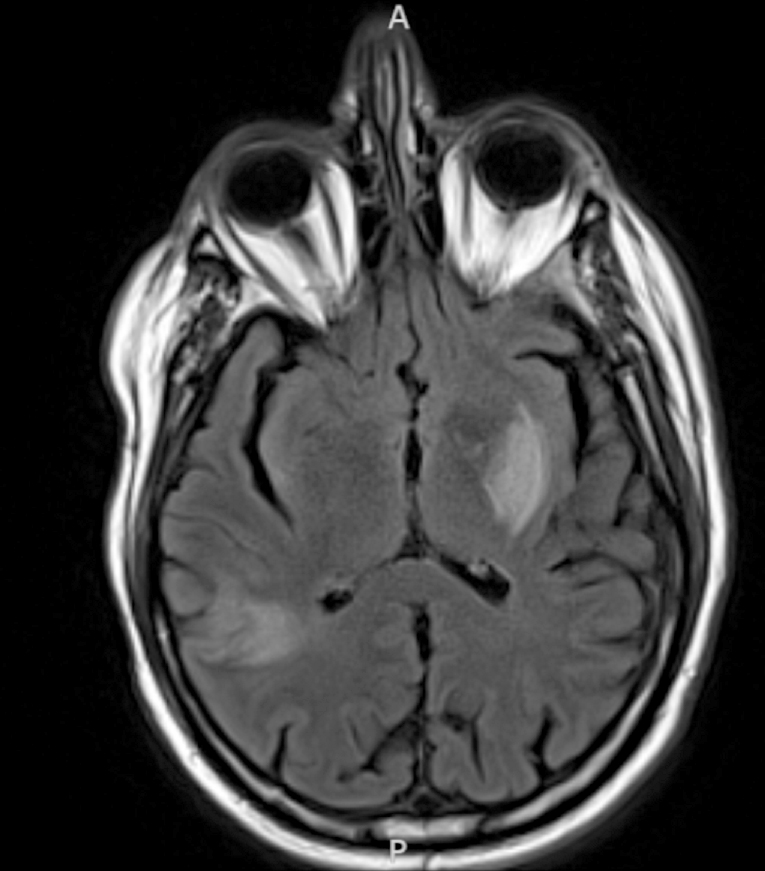

Radiology description

- CT unenhanced

- Early / acute signs: loss of definition between gray and white matter, cortical hypoattenuation and effacement of the sulci (Radiology 2005;235:444)

- Loss of the insular cortex in acute middle cerebral artery (MCA) infarcts (Radiology 1990;176:801)

- Hyperdensity of the MCA (i.e., hyperdense artery sign) is observed in 30 - 40% of patients with acute MCA infarcts (Stroke 1992;23:317)

- Chronic infarcts show cavitation sometimes with mineralization

- MRI

- Diffusion weighted imaging (DWI): hyperintense signal in the acutely infarcted tissue; low signal on apparent diffusion coefficient (ADC) map

- Infarcts are often T2 hyperintense

- Collateral flow on FLAIR: linear or serpentine hyperintensities distal to the site of obstruction (Neurology 2009;72:1134)

- Perfusion weighted imaging (PWI) - DWI mismatch: used to estimate the salvageable tissue (i.e., penumbra) in acute infarct (Neuroimaging Clin N Am 2021;31:177, AJNR Am J Neuroradiol 2015;36:32)

- Ischemic areas on PWI are compared with areas shown by DWI (i.e., the infarct core or nonsalvageable tissue); the mismatch represents the volume of salvageable tissue with reperfusion therapy

- Chronic infarcts show absence of contrast enhancement in strokes older than 4 months (Radiographics 2012;32:1285)

Radiology images